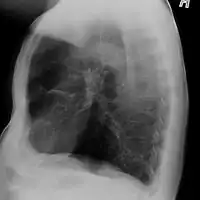

Alpha-1-antitrypsin deficiency/lateral radiograph lungs

Emphysema due to alpha-1 antitrypsin deficiency